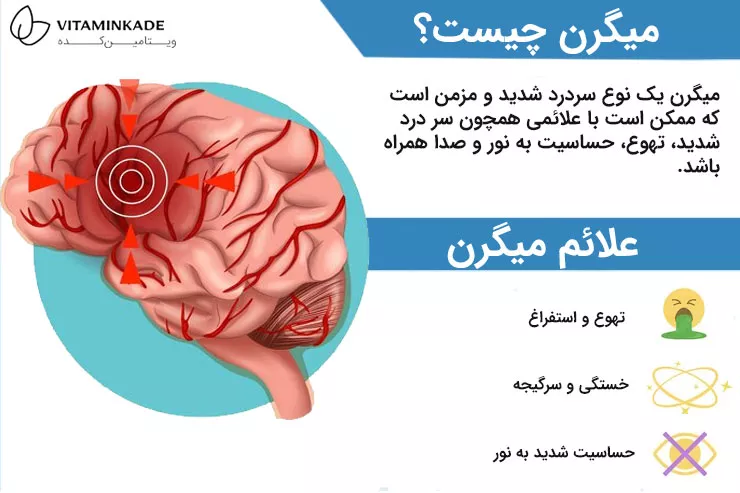

قرص مگنیفورت چیست | فواید،زمان مصرف و عوارض مگنیفورت

اگر تا حالا دچار میگرن،اسپاسم عضلانی و دردهای نوروپاتیکی شده باشید حتما با قرص مگنیفورت آشنا هستید.کپسول مگنیفورت مکملی شناخته شده با فواید درمانی زیادی برای سلامت سیستم عصبی و…